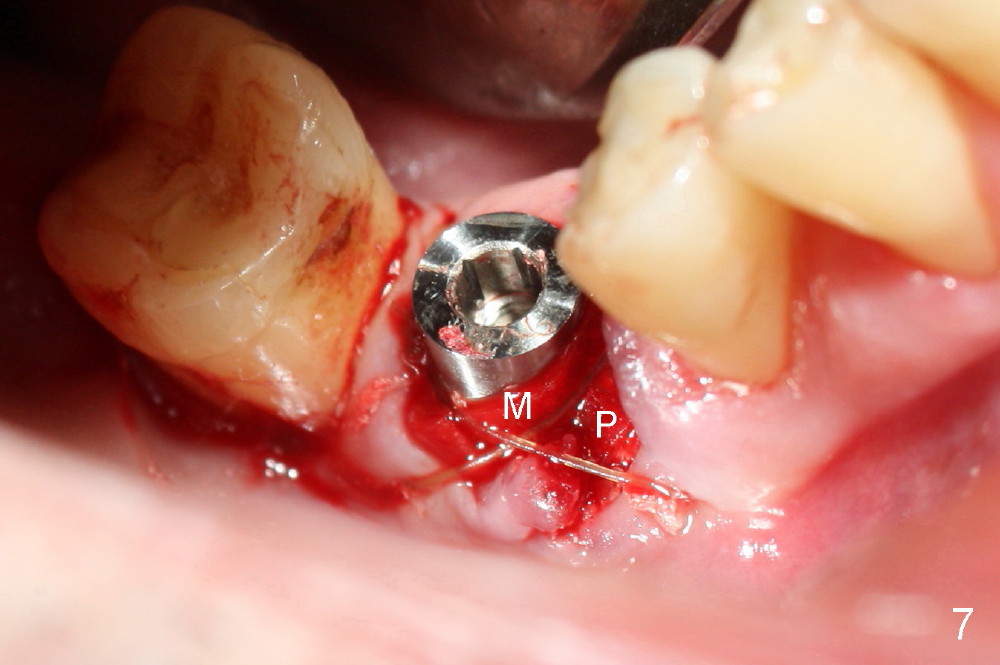

As to where to place an implant, we try to engage the largest tap (8 mm in diameter) into the mesial socket without binding. The buccal plate of the mesial socket is missing. It is risky to extend osteotomy in the mesial socket. Besides, the septum (Fig. 4 S) is not as tall as the distal socket (D). It appears that the distal socket is the safest place to place an implant. Furthermore, no drill is used for distal osteotomy. Instead two osteotomes (3.5x15 and 4x15 mm tapered osteotomes) are used to expand the distal socket with intention to push the septum mesially. Since the bone density is high, the osteotomes seem not to work as effectively as expected. Then a 4.5x17 mm tap is placed at the depth ~ 14 mm with stability (Fig.5). Finally a 5x14 mm tissue-level implant is placed with insertion torque >60 Ncm (Fig.6). Allograft is placed in the mesial socket and buccal aspect of the distal socket, followed by insertion of collagen plug and membrane (Fig.7). After insertion of an abutment (Fig.8 (taken 6 days postop) *), perio dressing (P) is applied to cover the wound. There is no postop paresthesia.